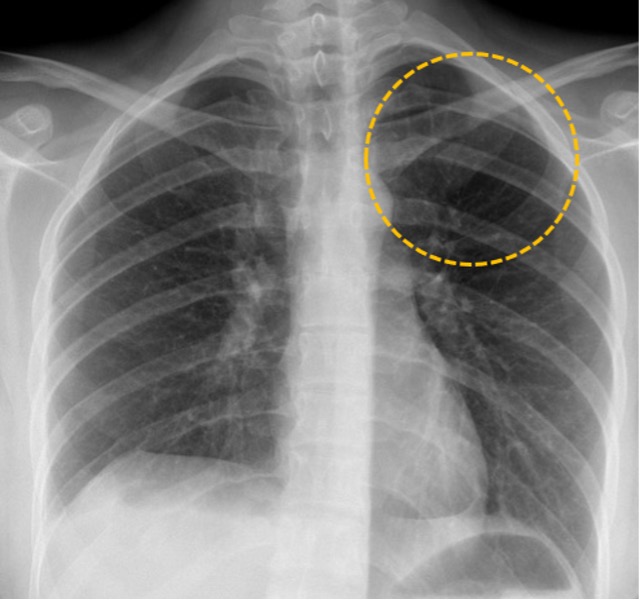

In a 1938 paper published in Acta Radiologica, Nils Westermark described the findings of pulmonary thromboembolism on a chest X-ray. He explained that blood flowing through the lung vessels appeared as finely branching opacities. When a clot obstructs blood flow, these fine opacities are absent, causing the affected lung area to appear very subtly darker in a wedge-shaped pattern on the X-ray film. This sign, although not very sensitive (14%), has been described to have a specificity of 92% in a 1993 study by Worsley et al. This finding of decreased density due to regional pulmonary oligemia (medical-speak for a localised decrease in blood flow in a part of the lung) came to be known as Westermark’s sign and, nearly a hundred years later, radiology residents across the world continue to be quizzed about it on their exams.